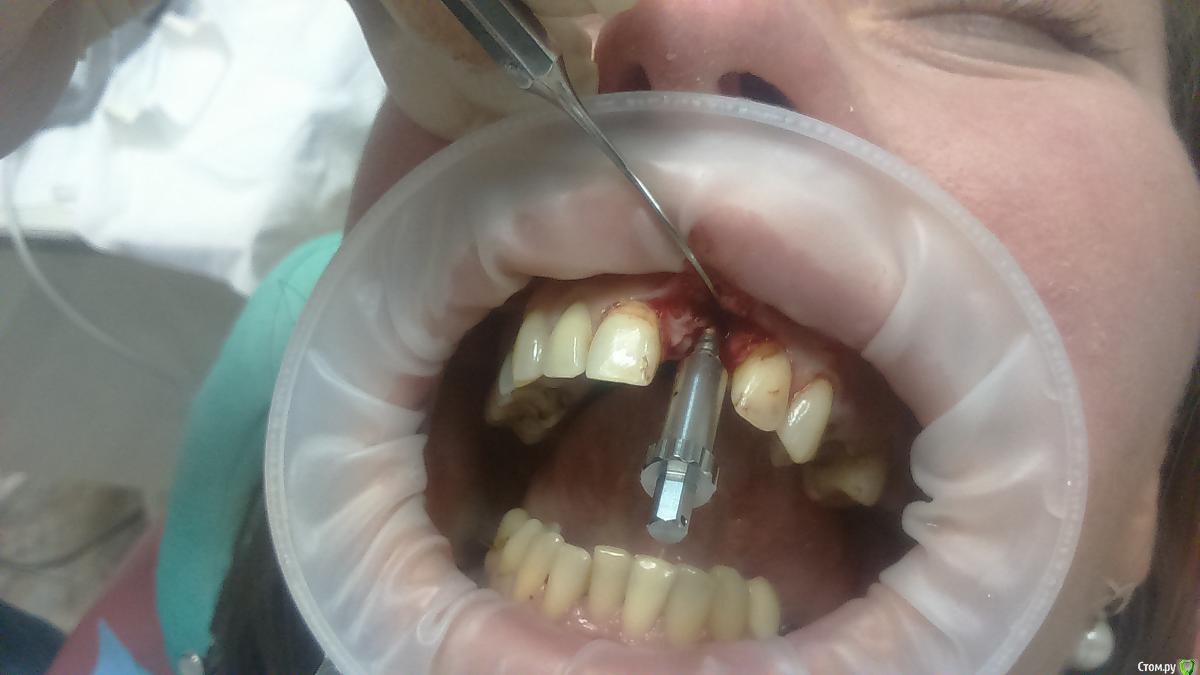

Platon Опубликовано 31 января, 2016 Автор Поделиться Опубликовано 31 января, 2016 Продолжение.не судите строго за фото, первый раз вообще фоткаю операцию)спасибо за советы.По порядку. После того, что мне написали, я решил все -таки уговорить на конусный имплантат (3.7-11.5 ImplantDirect). Также ортопед не хотел делать временную коронку, сказал что сделает каппу, птичку в топку -тоже сделали. Слизистая в области 21 была в рубцах. Исходя из этого всего я решил, коль временной коронки не будет, то сст подсаживать тоже не стану пока,(ортопеда уговаривал сделать временную коронку)))- торк был хороший 35-50н) для того чтобы сст попрактиковаться, но(((.в итоге, анестезия, разрез, сверло пилотное и сверло 2.2, далее расщепление с помощью набора майзенгер с использованием спредеров до нужного диаметра, установил имплантат, торк контролируемый, можно было подобрать любой) в итоге оставил 35. заглушка, совсем немного ксено, мембрана, ушился. ждем. Будет что-то типо каппы которая слегка отдавливает десну,формируя сосочки. не знаю, ни разу такую еще не видел.планирую на этапе раскрытия все-таки сст и временную коронку увидеть.вот. через 4 мес. выложу, что получилось) Если есть советы, критика, всему буду рад, спасибо 3 Ссылка на комментарий